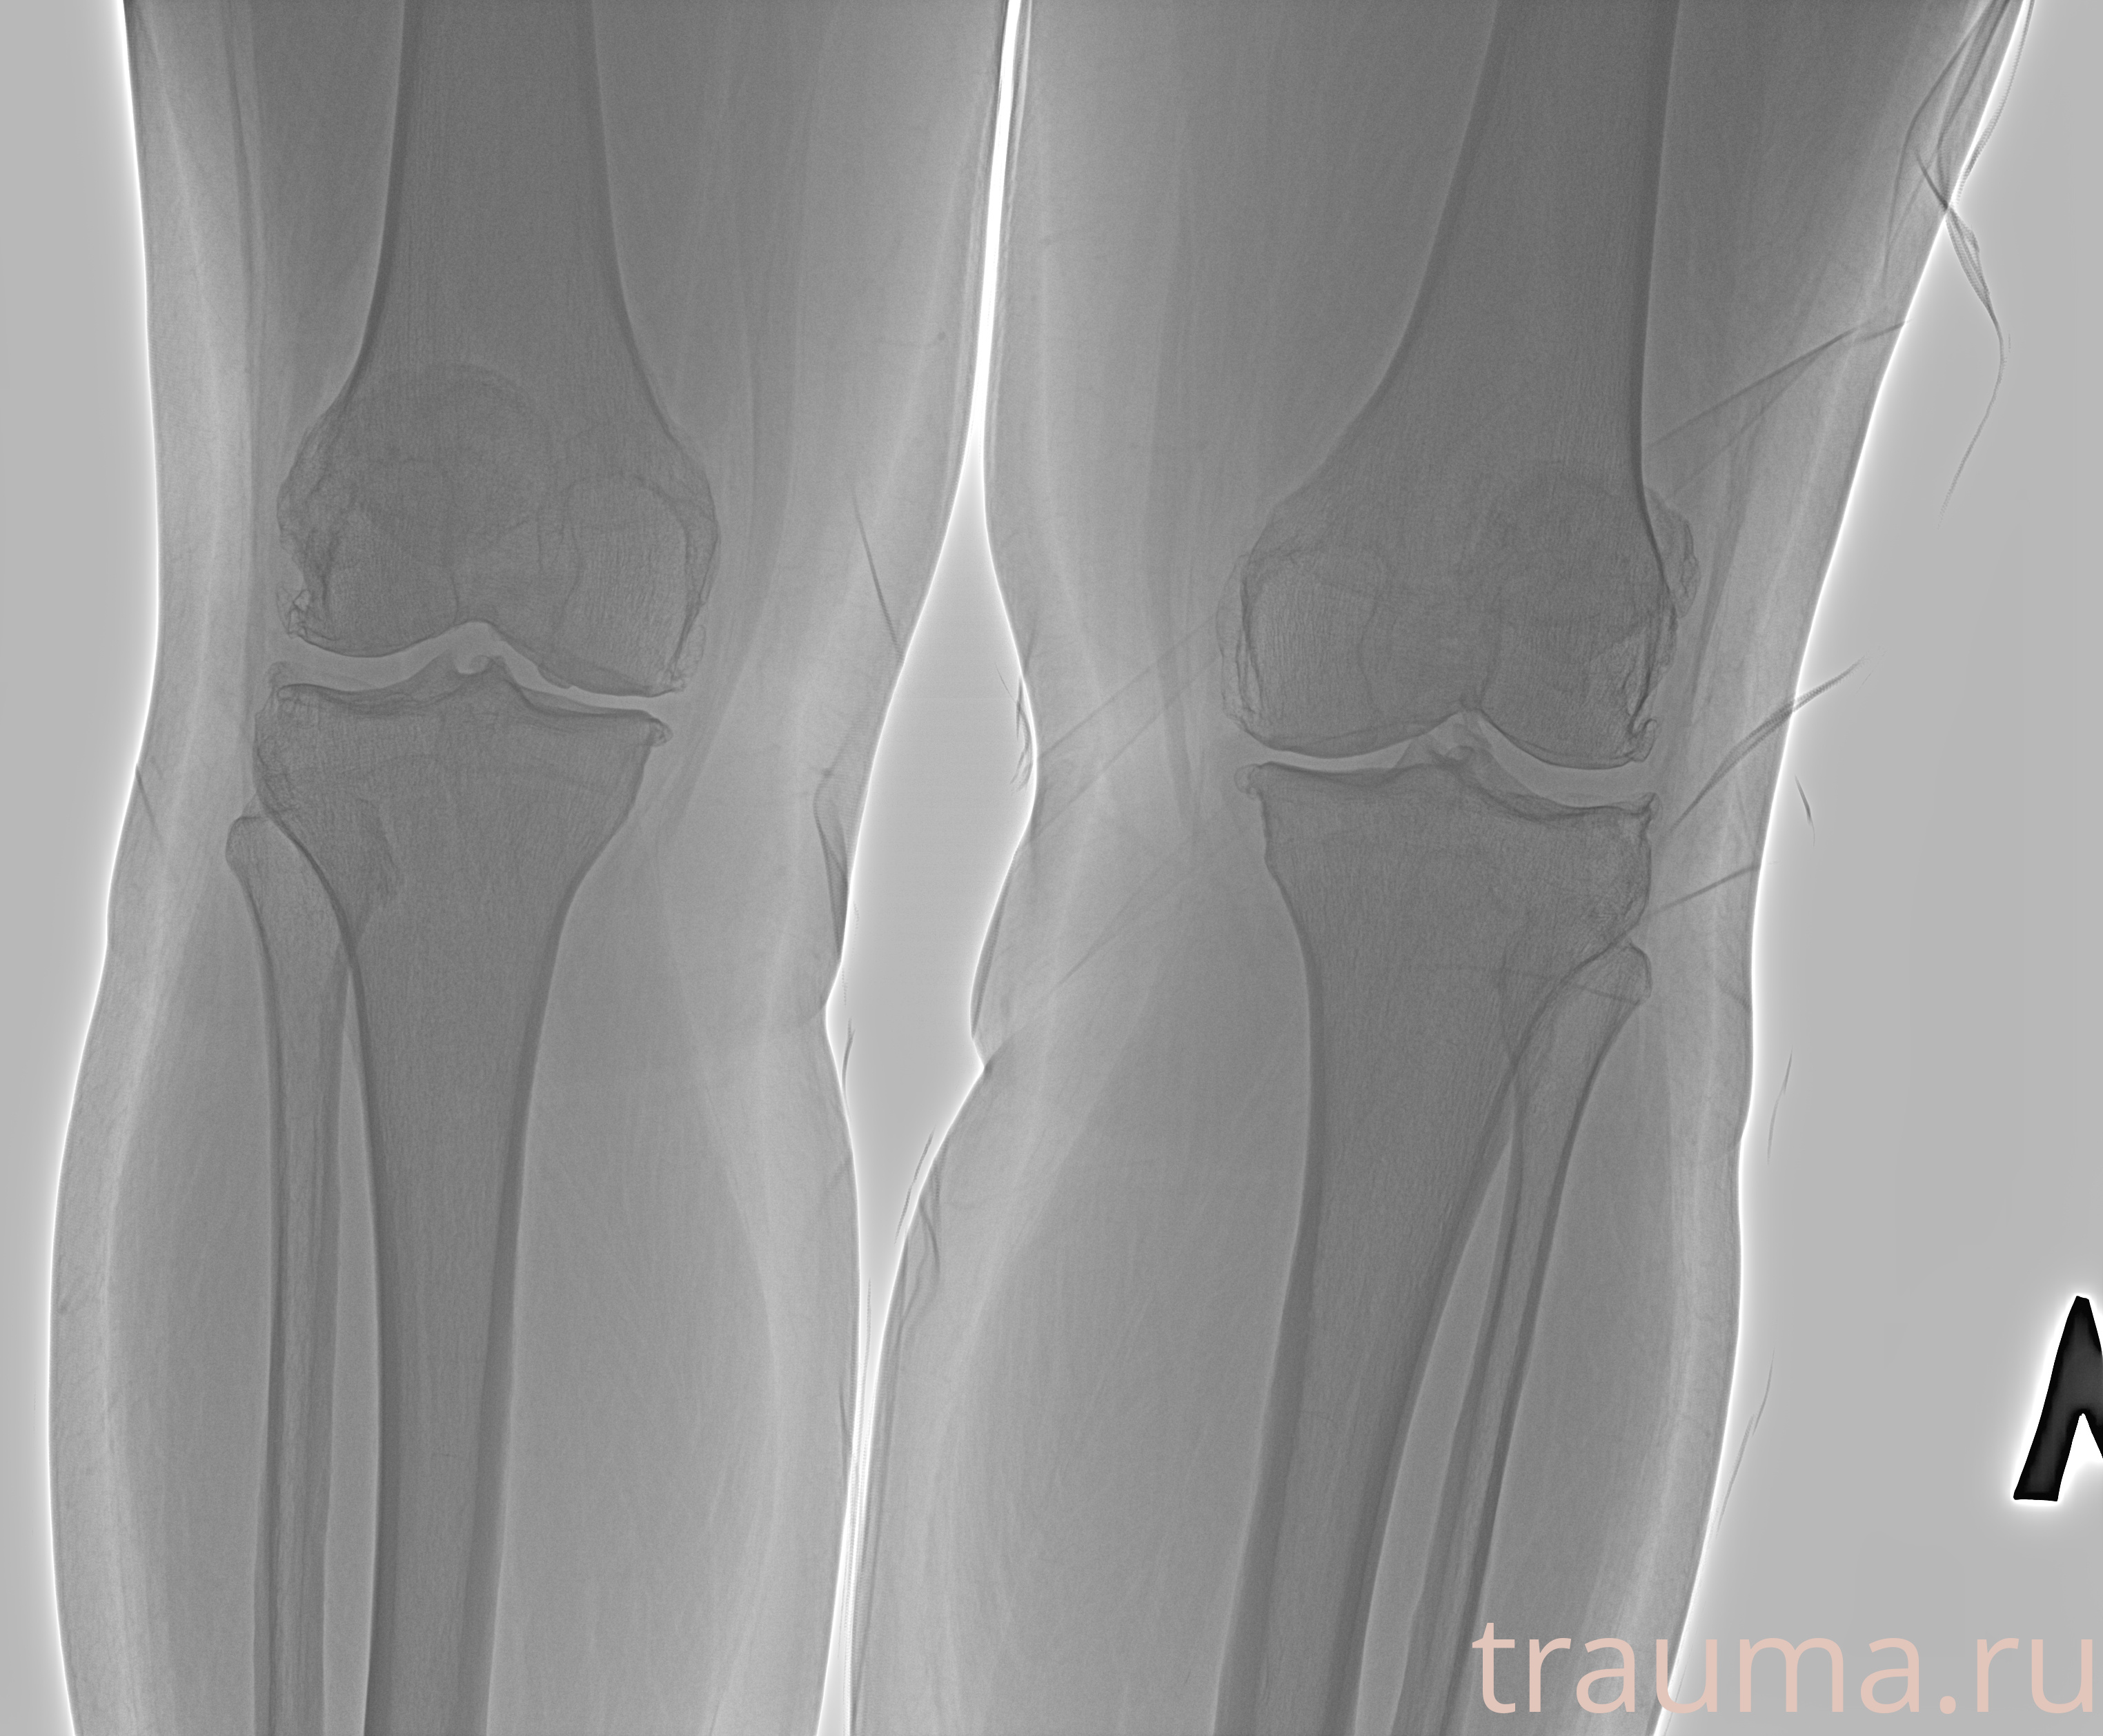

Рентген на дому: по вашему адресу приезжает врач-рентгенолог, травматолог-ортопед с мобильным рентгеновским аппаратом, проводит диагностику травмы или заболевания, делает необходимые рентгенограммы, дает рекомендации по дальнейшему лечению. Получить качественные снимки в домашних условиях возможно благодаря уникальной методике, разработанной МосРентген Центром для института  Склифосовского